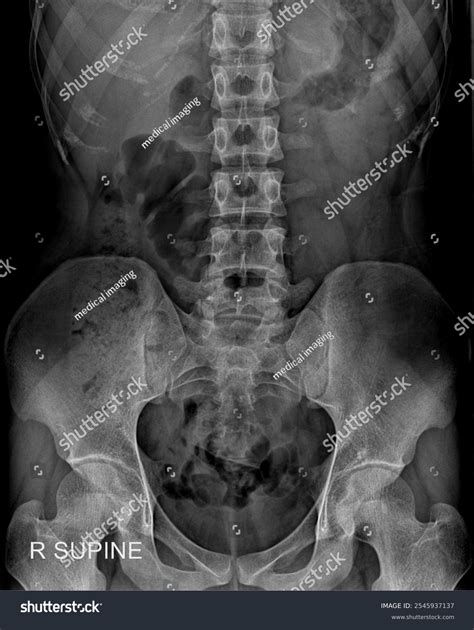

A Kub Abdominal X Ray, also known as a KUB (Kidneys, Ureters, Bladder) X-ray, is a type of abdominal radiograph that provides a detailed view of the abdominal cavity. This imaging technique is commonly used to assess the organs and structures within the abdomen, including the kidneys, ureters, bladder, intestines, and other soft tissues. The primary goal of a Kub Abdominal X Ray is to detect abnormalities such as obstructions, infections, or tumors.

Interpreting the results of a Kub Abdominal X Ray requires expertise in radiology. The radiologist will look for various signs and abnormalities, including:

• Air or gas patterns in the intestines

• Presence of foreign objects or obstructions

• Abnormalities in the shape or size of organs

• Signs of inflammation or infection

• Calcifications or stones in the kidneys or bladder